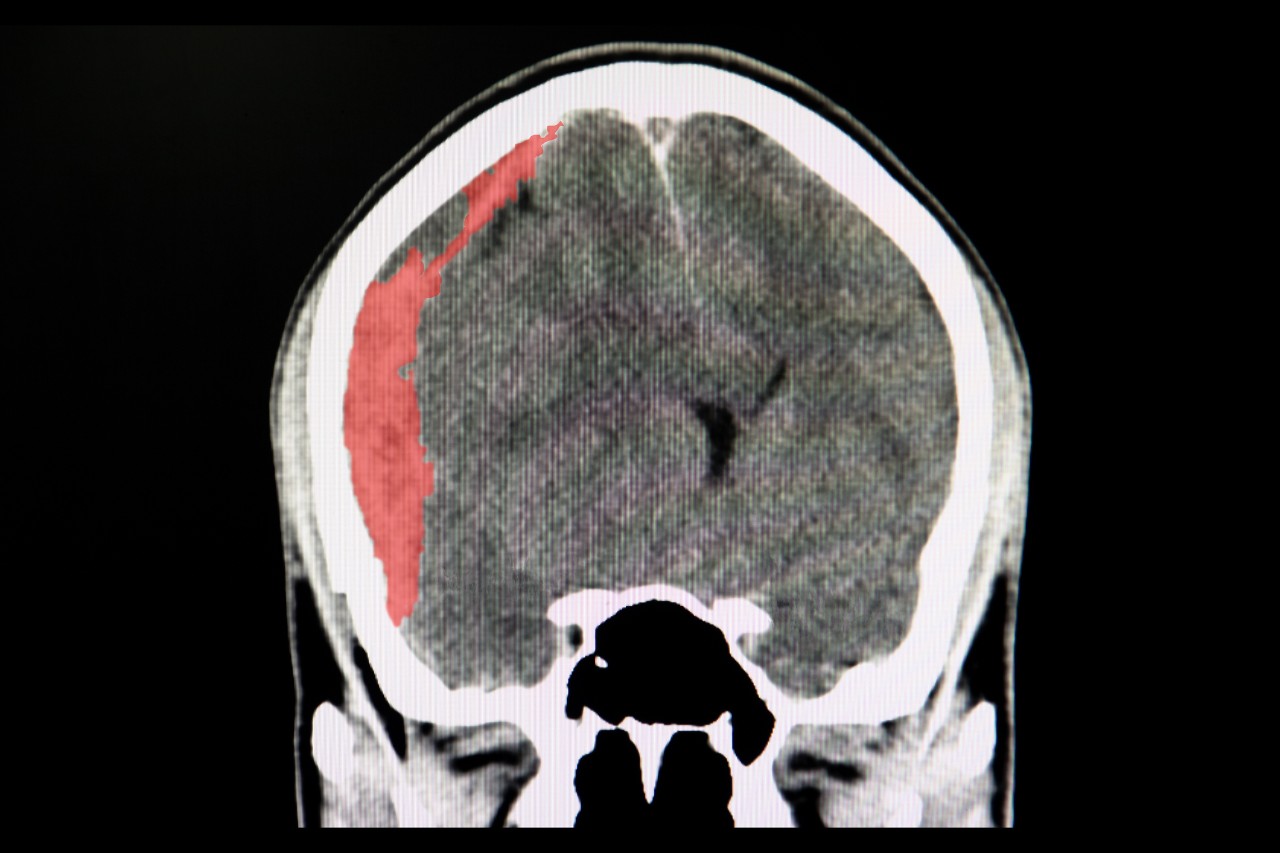

Up to half of all patients with subdural hematomas die or are severely disabled within one year of diagnosis. And although rates of this type of intracranial bleeding are rising in the American population, little research has focused on them.

Robinson said subdural hematomas can be caused by major head traumas such as car accidents, but they are also associated with minor falls in which people do not directly hit their heads. Bleeds like these are more common in elderly people.

Featured photo at top of a head CT scan displaying a subdural hematoma. Photo/Sopone Nawoot/iStock Photo.